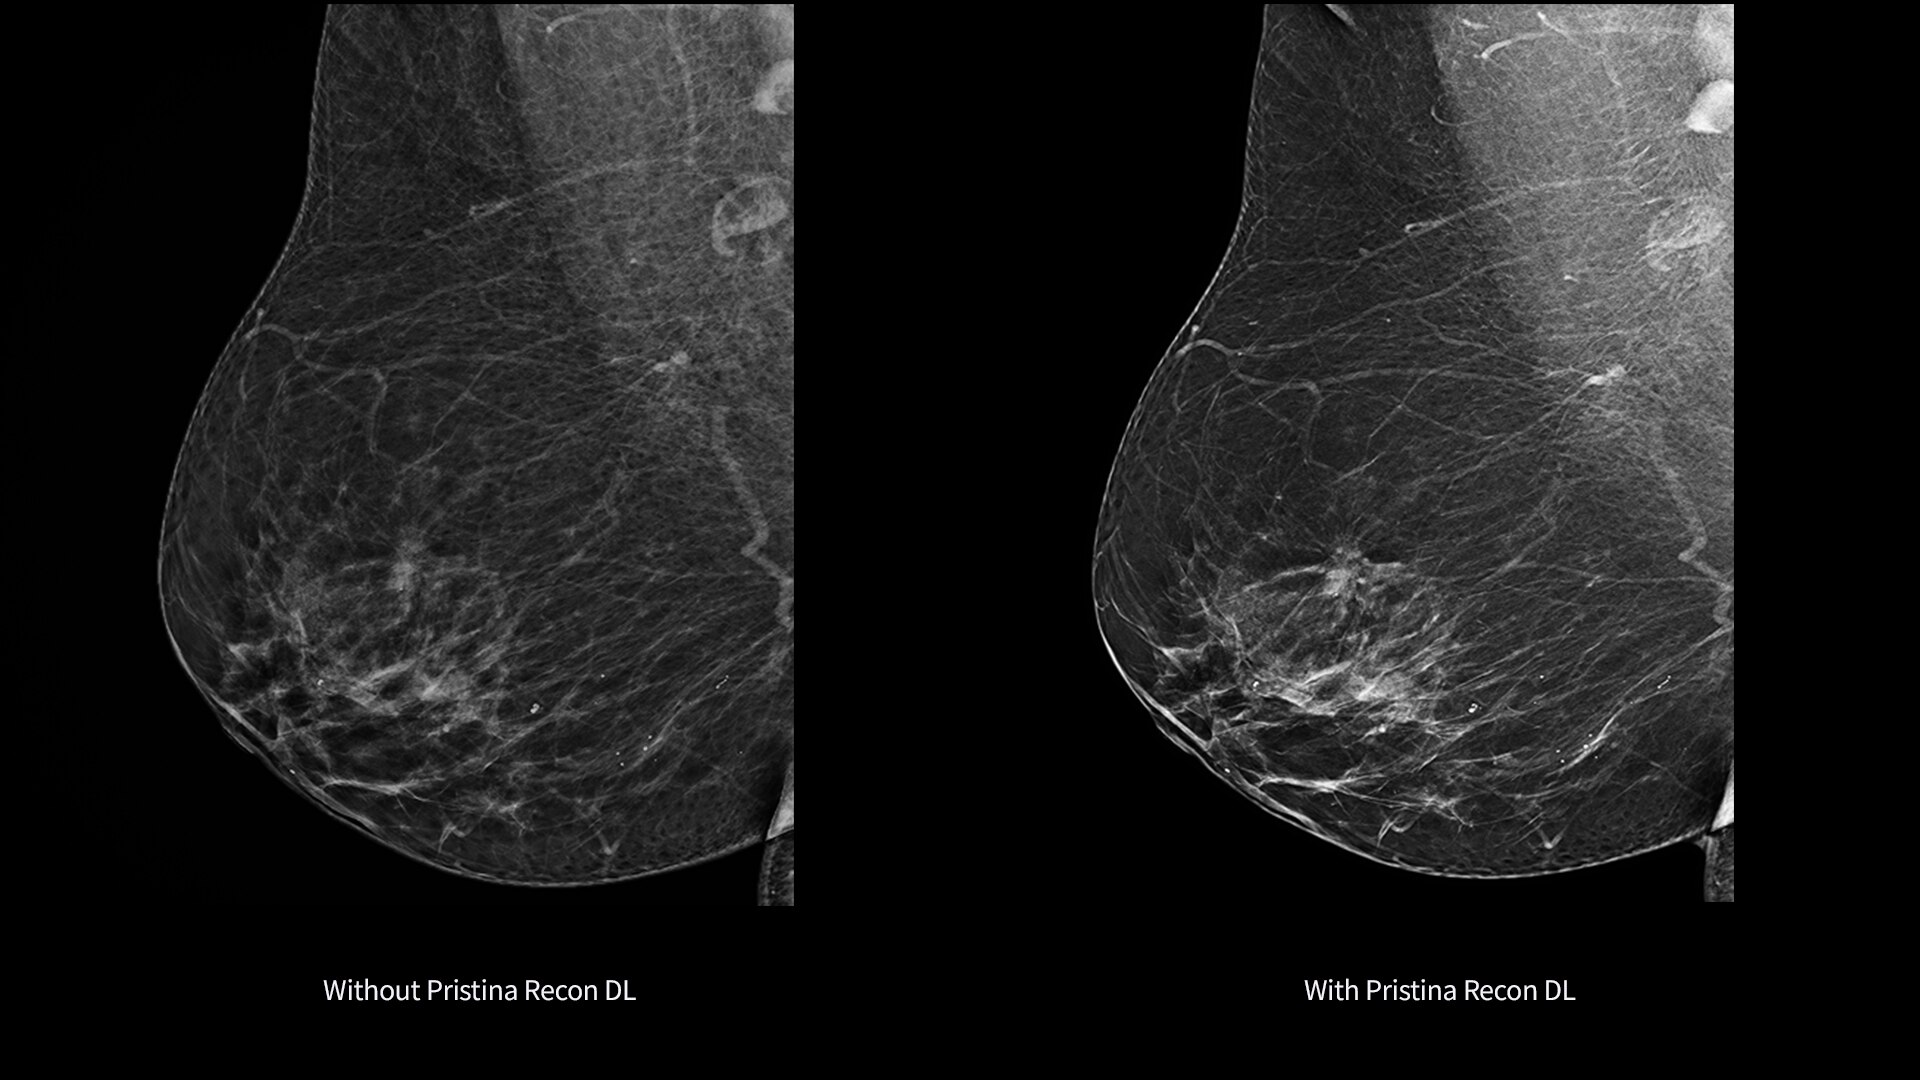

Pristina Recon DL gives you the power to detect and confidence to decide.

It pushes the limits of 3D mammography, delivering images with greater purity.

Born from GE HealthCare's pioneering AIR Recon DL in MRI, it represents a paradigm shift in image reconstruction.

Its dual deep learning technology reveals fine details minimizing artifacts and perceived noise1,2, without increasing dose.

Pristina Recon DL reconstructs with scientific precision, transforming breast images into pristine, clear volumes. It uses two deep learning models to improve image quality without changing the acquisition.

The improvement is easy to see, with radiologists surveyed consistently preferring its sharpness1,2 and lesion conspicuity1,2.